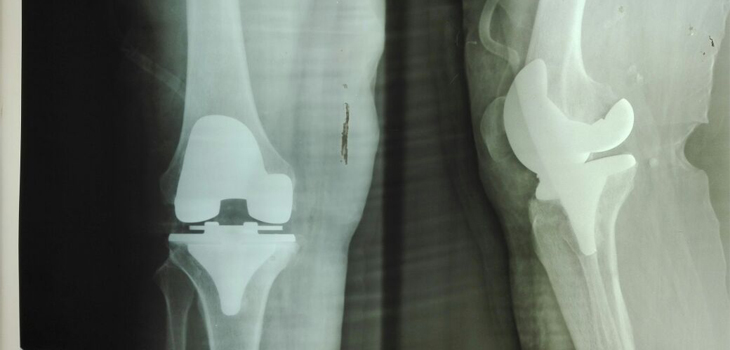

Realizará SS Jornada Protésica de Rodilla y de Cadera

Xalapa, Ver., 26 de junio de 2016.- Como parte del trabajo coordinado entre la Secretaría de salud (SS) y el Patrimonio de la Beneficencia Pública federal y estatal, del 27 de junio al 04 de julio se realizará la primera de dos jornadas protésicas de rodilla y de cadera, que permitirán mejorar la calidad de vida de 41 personas de 22 municipios veracruzanos.

El Centro de Alta Especialidad (CAE) Dr. Rafael Lucio, de Xalapa, y el Hospital de Alta Especialidad de Veracruz (HAEV), serán las instituciones sede para practicar las cirugías, informó el subdirector del Patrimonio de la Beneficencia Pública de Veracruz, Iván Alemán Chang, al señalar que el programa no tiene costo para los beneficiados.